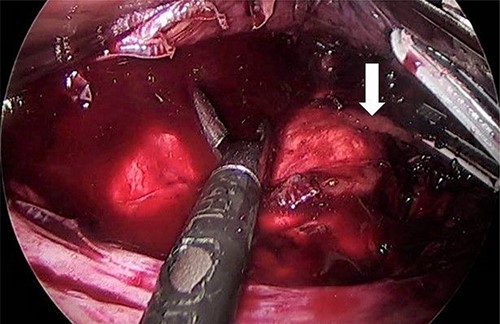

As for the LRA, ports are inserted in similar fashion as the LLA but with more to the right side. An additional port at the right midclavicular line is an optional (Fig. 5). In Patient 1, we started with the LLA to control the blood pressure caused by the adrenal gland and to prevent unnecessary bleeding from occurring. Conversely, we started with LSG in Patient 2 because the priority was controlling his comorbidities by weight reduction. The right hepatic lobe was retracted to expose the subhepatic area. The right hepatic ligaments were released, exposing the inferior vena cava. Dissection lateral to the IVC was continued exposing the right adrenal (Fig. 6). Complete dissection of the adrenal gland was completed and the pedicle was controlled using energy device (Fig. 7). There was constant communication with the anesthesia team during the surgery. After complete dissection of the adrenal gland, it was placed in the endobag and the LSG was conducted similar to the above-mentioned steps (Fig. 8).